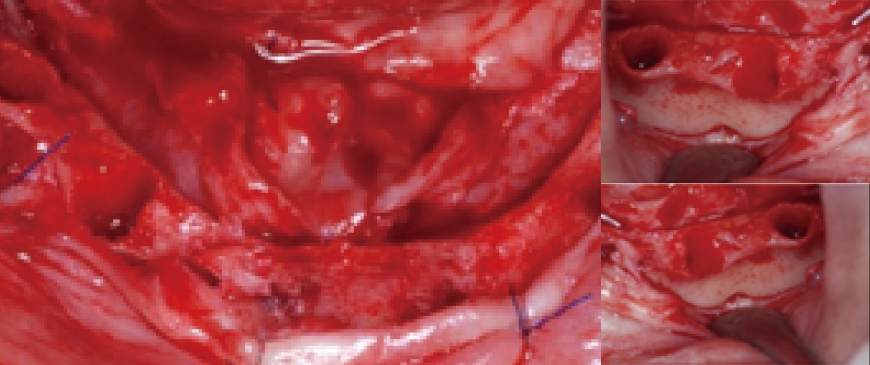

Fig 3

Upon flap elevation, it was confirmed that the first molar region also exhibited a significantly thin ridge condition.

Fig 4

In cases of thin ridges, immediate drilling can be challenging due to the risk of slippage. To improve drilling accuracy and stability, a small amount of bone can be removed at the drilling point using a rongeur or similar instrument, making the drilling process significantly easier and more controlled.

Fig 5

The osteotomy for three implants was completed, including the extraction socket of the second premolar. In the second molar region, the ridge had sufficient width, preventing dehiscence. However, in the extraction socket of the second premolar and the thin ridge area of the first molar, dehiscence occurred. Under conventional treatment protocols, active GBR (Guided Bone Regeneration) would typically be required to address these defects.

Fig 6

The three fixtures have been successfully placed. The BD Cuff implant in the second premolar extraction socket effectively covers the socket defect with its machined cuff. Additionally, the BD Cuff in the first molar region ensures that even if the thin buccal cortical bone undergoes resorption, the threads will remain covered, allowing for healthy and long-term functional stability.